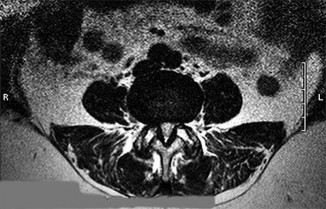

A 45-year-old male presents with severe shooting pain down his right anterior thigh and prominent weakness in knee extension. The right patellar reflex is absent.

MRI demonstrates a far-lateral (extraforaminal) disc herniation at the L4-L5 level. Which nerve root is most likely compressed?

A 45-year-old male presents with severe radiating leg pain. MRI of the lumbar spine reveals a far lateral (extraforaminal) disc herniation at the L4-L5 level. Which nerve root is predominantly compressed by a herniation in this specific location?

Explanation

A 45-year-old male presents with acute, severe right leg radicular pain. MRI of the lumbar spine reveals a far lateral (extra-foraminal) disc herniation at the L4-L5 level on the right side. Which nerve root is most likely compressed, and what clinical finding is expected?